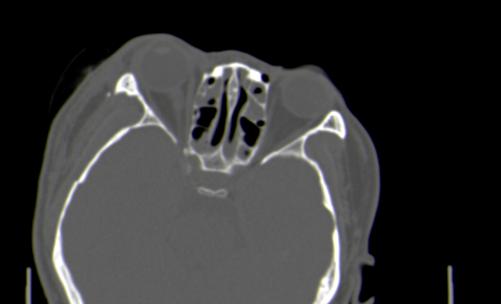

以下是引用皎皎白驹在2006-11-29 8:48:00的发言:[br]影像表现:双侧筛窦和上颌窦、鼻腔内均密度增高,右侧视神经增粗、弯曲,左筛窦顶部筛板及右侧纸板近视神经孔区可见骨折线。[br]结合临床表现考虑:右侧筛窦纸板近视神经孔区骨折致右侧视神经损伤。最好做个眼眶冠状扫描,更明确右侧视神经管是否狭窄。

以下是引用w_jianhua在2006-11-29 10:07:00的发言:[br]影像表现:双侧筛窦和上颌窦、鼻腔内均密度增高,右侧视神经增粗、弯曲,左筛窦顶部筛板及右侧纸板近视神经孔区可见骨折线。[br]结合临床表现考虑:右侧筛窦纸板近视神经孔区骨折致右侧视神经损伤。最好做个眼眶冠状扫描,更明确右侧视神经管是否狭窄。 [br] [br]支持[br]

以下是引用守望可可西里在2006-11-29 9:46:00的发言:[br][quote]以下是引用皎皎白驹在2006-11-29 8:48:00的发言:[br]影像表现:双侧筛窦和上颌窦、鼻腔内均密度增高,右侧视神经增粗、弯曲,左筛窦顶部筛板及右侧纸板近视神经孔区可见骨折线。[br]结合临床表现考虑:右侧筛窦纸板近视神经孔区骨折致右侧视神经损伤。最好做个眼眶冠状扫描,更明确右侧视神经管是否狭窄。